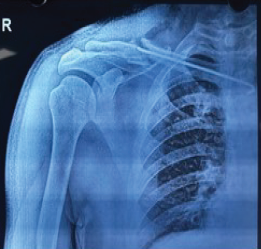

From Nail to Fail: Complications Encountered with Clavicle Nailing – A Series of 3 Cases

S Udayan , S Srijay Sashaank , Mohamed Sameer , J K Giriraj

………………………………p.250-255